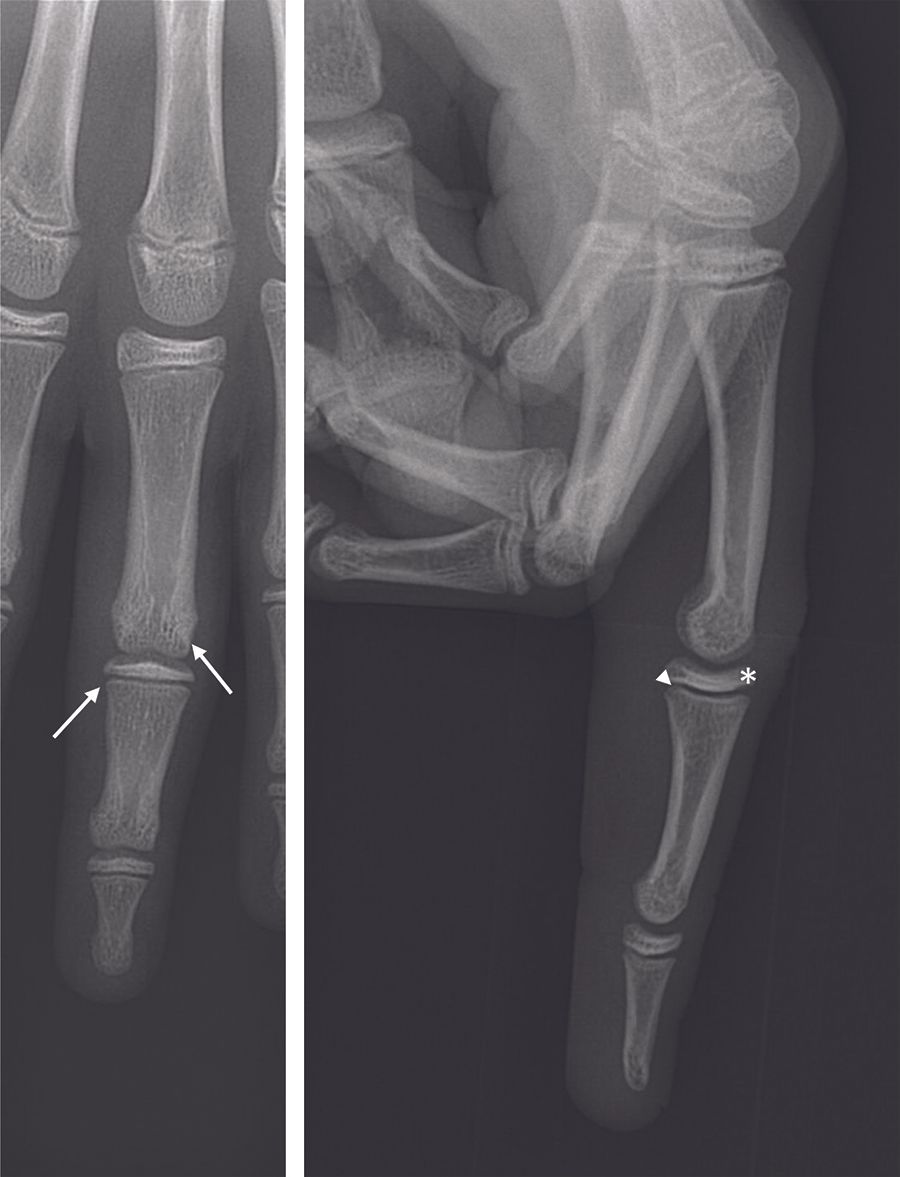

Technique Traumatismes de l'articulation interphalangienne proximale des doigts longs en pédiatrie , C.N. Steiger Centre Chirurgical Émile Gallé, CHU Nancy, 54000 Nancy , Gilles Dautel Hôpital d'Enfants, CHU Brabois, Vandoeuvre, France N°278 - Novembre 2018 - Cahier 1 ● 13 min de lecture